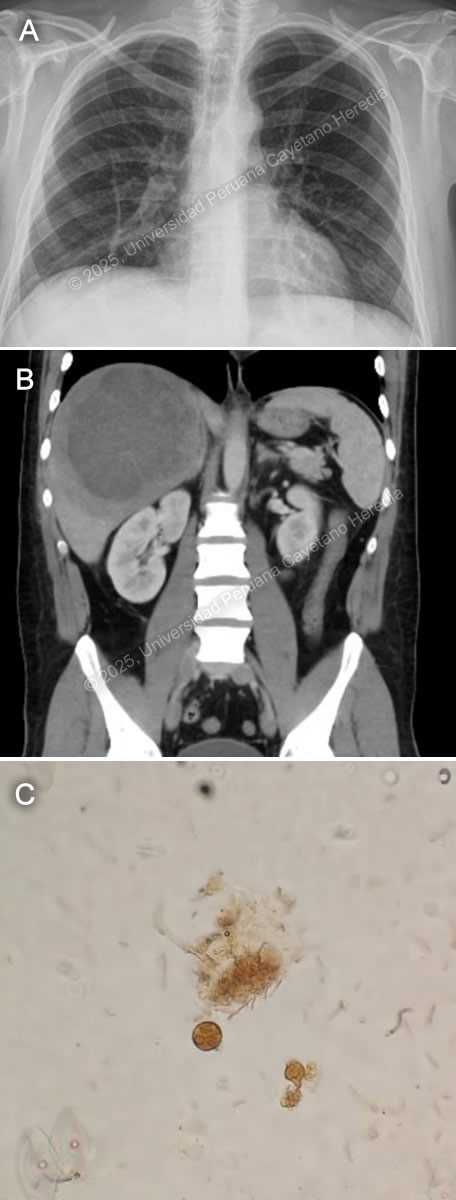

![]() History: A 21-year-old male patient with no significant past medical history presented to the emergency department of HCH with a 5-month history of cough and chest pain. Five months before admission, he presented sporadic dry cough and occasional mild left pleuritic chest pain. He attended an occupational medicine consult where a routine chest X-ray was performed, revealing a radiopaque circular lesion in the left hemithorax (Image A), and a follow-up chest CT confirmed the presence of a 72x98x68mm left-sided pulmonary lesion and an additional right-sided 19x18x23mm hyperdense pulmonary lesion (Image B). Three weeks before admission his cough became productive with whitish sputum and was associated with shortness of breath on exertion. Ten days before admission, the pleuritic pain intensified and disrupted his sleep. Five days before admission, he presented a cough with blood-tinged sputum, generalized malaise, and subjective fever. Due to the persistence of symptoms, he traveled to Lima and attended the ED. Epidemiology: The patient was born and lives in Oyon, a city in northern Lima province at an altitude of 3600 meters above sea level. He lives in a rural area where he works as a mechanic and on his family’s farm, feeding, cleaning, and caring for sheep, cows, cats, and dogs. The dogs live inside the house and are fed on the dead sheep’s viscera. He has only traveled to rural areas nearby. He has no known TB contacts and no other family members have presented similar symptoms. Physical Examination on admission: BP was 100/60 mmHg, RR 28, HR 92, afebrile at 37°C with a Sp02 of 90% on room air. Breath sounds were abolished in the left hemithorax, and there was hyper resonance to percussion in the upper 2/3 and dullness in the lower 1/3 on the left hemithorax. The rest of the exam was normal. Laboratory: Hemoglobin was 17 g/dL (13-16 g/dL), WBC 17 100/uL (4-12 x 10^3/uL) with no bands, 51.6% neutrophils, 15.9% lymphocytes, 27% eosinophils (absolute count: 4 595, normal being less than 500/uL), 0% basophils, 4.9% monocytes. Platelets 391 000/uL. Urea 29 mg/dL, Creatinine 0.83 mg/dL, Sodium 142 mEq/L (135-145 mEq/L), Potassium 4.35 mEq/L (3.5-5.5 mEq/L), Chloride 107 mEq/L (96-106 mEq/L). Total bilirubin 0.53 g/dL with a direct of 0.32 g/dL. AST 14, ALT 24 IU/L (normal less than 40 IU/L). CRP 4.6 mg/dL (normal less than 0.3 mg/dL). PT 13.5 sec, PTT 29 sec with an INR of 1.15. HIV test was negative and VDRL was non-reactive. Imaging: A chest X-ray was performed on admission (Image C) followed by a normal abdominal ultrasound. UPCH Case Editors: Carlos Seas, Course Director / Mario Suito, Associate Coordinator |

![]() ![]() Discussion: The chest X-ray on admission revealed a left side hydropneumothorax with a ruptured cyst on the left lung base showing the “water lily” sign (Image C, red arrow), which was more evident on chest imaging after chest tube insertion (Image D). Western Blot for Echinococcus granulosus was positive for the 21kDa, 16kDa, and 8kDa antigens, confirming the diagnosis. PHD is the second most common manifestation of cystic echinococcosis (CE) representing 20-30% of all cases (1). CE has an annual incidence in endemic areas of 1 to 200 per 100,000 and a mortality rate of 2-4% (2), affecting countries from South America, Eastern Africa, Central Asia, and the Mediterranean (1). It is commonly found in impoverished rural areas. Most affected individuals have one or more risk factors, including living in unsanitary conditions, raising livestock such as sheep, herding or guarding dogs often near homes that are fed offal, and slaughtering livestock close to humans and dogs (3). Echinococcus granulosus eggs are released by the adult tapeworms residing in the definitive hosts (canids, mainly dogs) GI tract that are ingested by humans who act as accidental hosts. Eggs hatch in the intestine, releasing oncospheres that enter the portal circulation or lymphatic system, reaching the liver, where they develop into hydatid cysts (metacestode larvae). The hydatid cyst is composed of an acellular laminar layer and an internal germinal layer that produces a clear hydatid fluid, protoscoleces, and daughter cysts, and is surrounded by a third membrane, the adventitial layer (pericyst), formed by the host immune reaction to the cyst and fibrous tissue. Oncospheres are usually trapped in the hepatic parenchyma, but some may travel through the liver sinusoids and pass through the hepatic veins and inferior vena cava, reaching the right heart and landing in the lungs or pass the lungs and through the left side of the heart reach other organs. PHD has a variable clinical presentation depending on location, size, and cyst wall integrity. It can be discovered incidentally since it can be asymptomatic until rupture, fistula development, mass effect, or other complications occur (4). Some symptoms and signs associated with cysts include shortness of breath, coughing, hemoptysis, pneumonia, atelectasis, and the expectoration of a salty fluid (‘’vomica’’) when a cystobronchial fistula is formed (5). Diagnosis is based on radiological findings and complementary confirmatory serology. Serology includes sensitive screening tests like enzyme immunoassays (EIA) and specific confirmatory tests like immunoblot (Western blot). Screening tests have a sensitivity of 80-100% for liver cysts but only 50-56% for lung cysts. Therefore, a high false-negative incidence rate must be considered, particularly for cyst stages where the host has not been exposed to the parasitic antigen (CE1) or for biologically inactive cysts (CE4, CE5) (6). Surgery is the cornerstone of therapy for PHD. It should be pursued first in the co-existence of pulmonary and liver cysts because of the higher risk of rupture and cystobronchial fistulas of the former (5). Treatment with albendazole 10-15 mg/kg divided into two doses can be started 1-3 days before surgery and continued 3 months postoperatively. In cases where the cyst contents spill into the pleural space either spontaneously or iatrogenically, as in our patient’s case, it is essential to begin antiparasitic treatment promptly alongside surgical intervention and thorough irrigation of the pleural space with isotonic saline to prevent secondary CE (5). Primary antiparasitic treatment without surgical involvement is usually avoided because of the risk of treatment-induced cyst membrane detachment, rupture, and opening of cystobronchial fistulas, except for small lung cysts less than 5 cm (7). References |